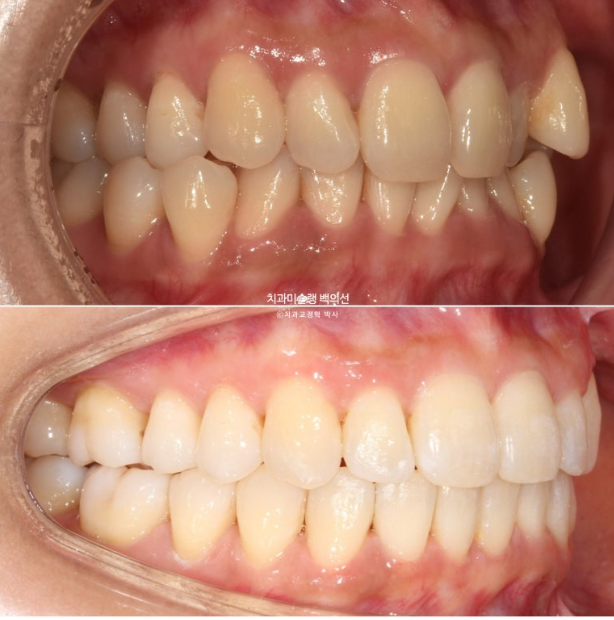

옥니, 덧니, 과개교합, 반대교합, 중심선 불일치 등 다소 복잡해 보이지만 환자분이 잘 껴주어 예상보다 치료가 빠르게 마무리된 케이스를 보겠습니다.

송곳니와 작은어금니 덧니가 보이며 작은어금니가 거꾸로 물리는 반대교합도 보입니다.

앞니 중심선은 약 2mm 어긋나 있습니다.

위 앞니가 아래앞니를 많이 덮어 깊게 물리는 과개교합도 있습니다.

덧니로 배열에서 튀어나와있는 치아들은 잇몸이 내려가 있습니다.

다행히 큰어금니 교합은 좋은 편

중심선이 맞아지고 과개교합도 해결되었고 아래앞니 치축 기울어짐이 보입니다.

덧니가 배열되며 반대교합도 해소가 되었습니다.

중심선, 과개교합, 덧니의 개선

옥니였던 앞니 각도가 정상각도를 찾았습니다.